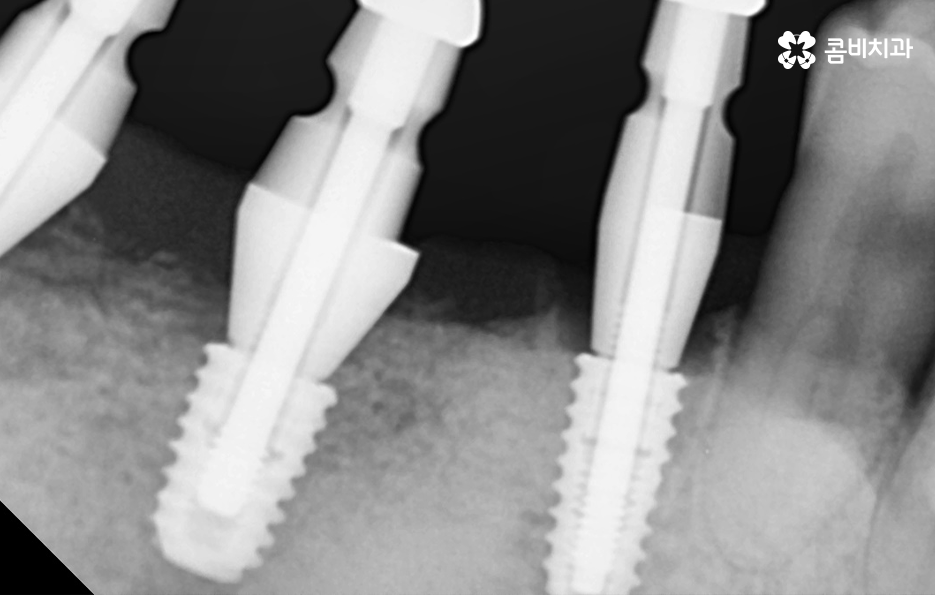

위 환자분의 케이스를 살펴보면 임플란트 시술 후 임플란트 주위염이 발생되어 이미 치조골이 상당히 녹았을 정도로 엑스레이 상에서도 관찰할 수 있어요

임플란트는 보편적으로 분리형이 주로 사용되고 있는데 임플란트의 인공치근은 잇몸 뼈와 골유착이 되어 단단하게 고정이 되어 있고 그 위에 지대주와 보철물이 연결되어 있는 형태이기 때문에 임플란투 수명에 있어서 임플란트의 인공치근 부분이 염증으로 인해 잇몸 뼈가 녹게 되면 임플란트 자체도 흔들리게 되고 결국 제거 후 재수술을 해야 될 수 있어요